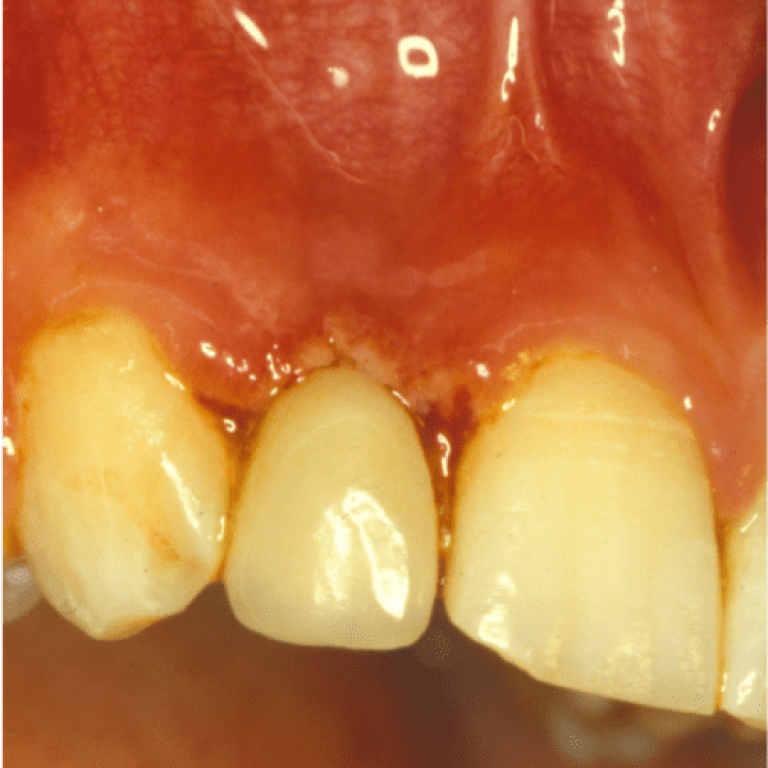

La bocca può essere interessata da molteplici malattie e può essere causa di affezioni a distanza che si …